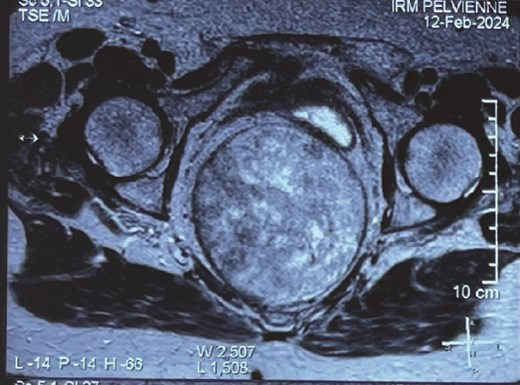

Pelvic magnetic resonance imaging (MRI) showed a voluminous, 12.5 × 10.5 cm, retro rectal mass exerting anterior compression on the rectum, displacing it laterally (Fig. 1).

In our case, imaging confirmed the presence of a well-defined, voluminous, retro rectal mass, hypo and hyperintense on T2-weighted images and hypointense on T1-weighted images.